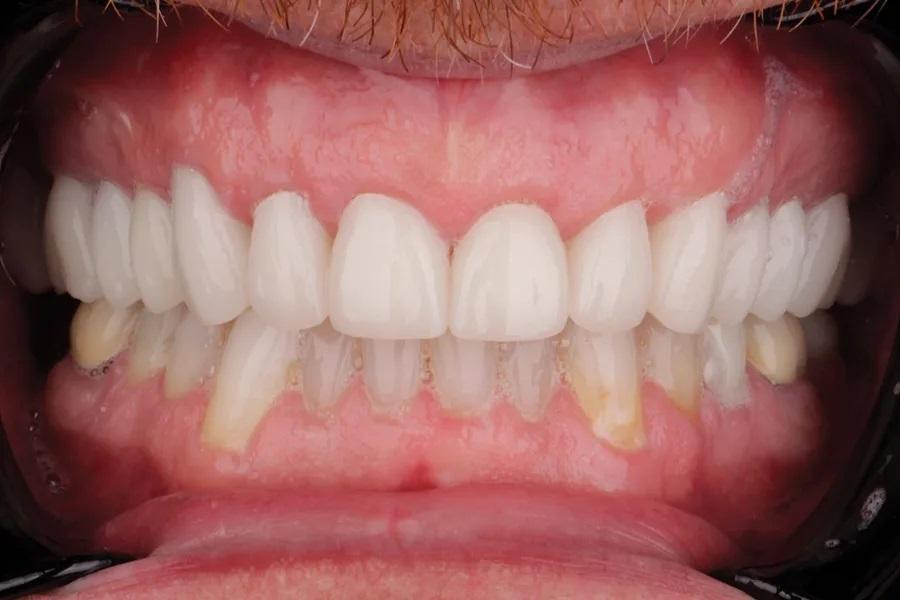

Мужчина, 45 лет. Основная жалоба — неловкость при улыбке из-за коротких, деформированных и измененных в цвете зубов. Обследование выявило гингивит с соответствующей потерей прикрепления, множественные кариозные поражения, износ зубов и реставраций (Фото 1 – Фото 3). Зафиксирован ограниченный паттерн жевания (ОПЖ), что определило умеренный функциональный риск и необходимость учета окклюзии в плане лечения.

Фото 2. Улыбка крупным планом до лечения.

Фото 3. Вид с ретракторами до лечения. Износ, истончение эмали, окрашивание зубов.